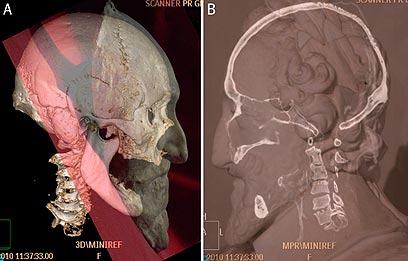

שימוש בפחמן רדיואקטיבי עזר לתארך את הראש לתקופה שבין 1450-1650, אשר תאמה את התקופה בה חי המלך – בין 1533-1610. מידע מדויק עוד יותר הגיע מהשימוש בסורקים מיוחדים ובצילומי רנטגן, שמצאו חתך באורך 5 מ"מ המקביל לפצע הדקירה שנגרם בשנת 1594 בניסיון ההתנקשות הקודם במלך.

A: הגולגולת בהשוואה ליציקת גבס של ראש המלך שנוצרה לאחר מותו. B: תמונת רנטגן של הראש בהשוואה לפסל המלך (צילום: רויטרס)